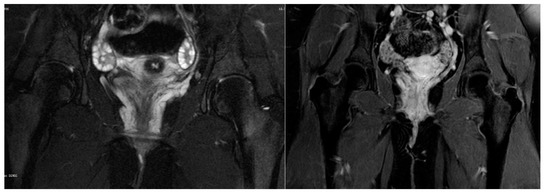

Vulvar varicosities in nonpregnant females, either isolated or as a part of the pelvic congestion syndrome, are rare. We present a case of an adolescent girl with morbid obesity with bilateral bluish protrusions on the labia minora, as an incidental finding, that coincided with her excessive weight gain. The adolescent underwent thorough clinical examination, doppler ultrasound, contrast venography and varicography, and magnetic resonance angiography to rule out alternative diagnoses. Imaging results confirmed the presence of large venous lakes. Venous drainage to the internal iliac vein and connections with the long saphenous vein were delineated. Incompetence, dilatation, or reflux of ovarian or internal iliac veins, or their main tributaries, were not noted. Since the adolescent was asymptomatic and other pathologies, such as vascular malformations or hemangiomas were excluded, she was managed conservatively with counseling about lifestyle modification and weight reduction. This is only the third reported case of vulvar venous varicosities in adolescents. Female sex, along with obesity, are known risk factors for varicose vein formation; however, the pathogenesis is not fully understood. Additional research is needed to elucidate the role of excess adipose tissue in the pathophysiology of vulvar varicose veins and to optimize diagnostic workup and management in adolescence. Full article

Background: Although pregnancy has been identified as one of the risk factors for venous disease, the mechanism of this interaction remains unclear. Possibly, pregnancy results in overstrain and vein dilatation, which exceed their durability and persist after pregnancy. The aim of this study was the assessment of the relationship between the number of pregnancies in women with venous disease and the selected parameters of their venous systems. Patients and methods: The retrospective assessment concerned 518 patients subjected to the diagnostics of the venous system in the lower limbs and the abdomen/pelvis using ultrasound scan and magnetic resonance or computed tomography. Results: We found that the occurrence of pelvic venous symptoms increases proportionally to the number of pregnancies and is correlated with ovarian and parauterine vein dilatation/incompetence (e.g., 13.5% of nulliparous women reported pelvic pain, and reflux in left ovarian veins was detected in 21.4% of the patients from that group, whereas in women after two pregnancies, pain and reflux concerned 22.8% and 90.6% of patients, respectively). In the nulliparous group, the development of venous disease resulted from the presence of anatomic abnormalities in abdominal/pelvic veins. Conclusions: Our report proved that the number of pregnancies is correlated with the incidence of pelvic vein insufficiency. Although not specifically addressed in this study, some correlation was found with saphenous disease as well. However, further studies are necessary to provide more evidence about the role of pelvic vein insufficiency in chronic venous disease of the lower limbs. Full article

Introduction: The current treatment of venous disease is focused on reflux elimination in main venous trunks, especially in the saphenous vein. However, a high recurrence rate, independent of the method of treatment, suggests that the reason of low effectiveness may be due to a strategy focused on symptoms, without considering their origin. Method: The aim of study was the comparison of retrospective data from 535 women with venous disease, either after treatment (n = 183) or not treated before (n = 352). The analysis concerned clinical symptoms and the results of the extended diagnostics, including the examination of the lower limb, pelvic and abdominal veins either using duplex-doppler ultrasound as well as venography with computed tomography or magnetic resonance. Results: The comparison of selected venous system parameters revealed more advanced disease progression in previously treated patients, compared to non-treated individuals (e.g., ipsi- or bilateral incompetence of sapheno-phemoral junction—29.5% vs. 20.4%, at P < 0.05 and 13.6% vs. 7.7% at P < 0.05, respectively). This difference could be explained by post-treatment alterations in the venous system, an older age and the higher number of pregnancies in the recurrence group. However, both groups did not differ in regards to the symptoms of pelvic venous insufficiency or the frequency of relevant variants/abnormalities in venous system. Conclusions: Based on the aforementioned findings, we postulate the revision of treatment strategy, which should consider abdominal and pelvic veins as the source of reflux in many female subjects. Full article